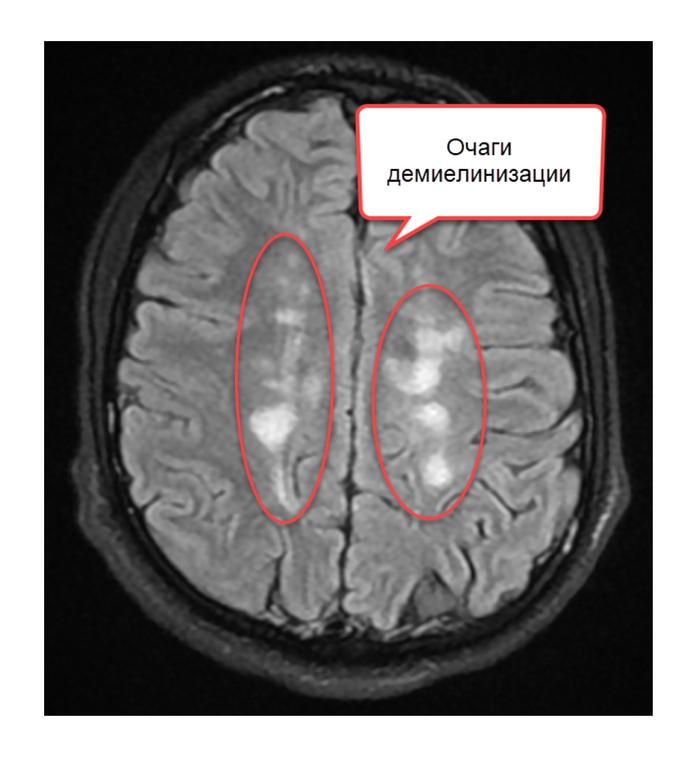

Симптомы перивентрикулярных очагов могут включать головные боли, изменения в работе мозга, эпилептические припадки и другие неврологические симптомы. Для диагностики таких очагов обычно используются различные методы обследования, такие как МРТ или КТ головного мозга.

Как уже было упомянуто, лейкоареоз можно увидеть на нейроизображениях КТ и МРТ головного мозга, сниженной и повышенной частотой соответственно.

Серия МРТ головного мозга включает в себя T2 и FLAIR и является наиболее распространенным методом для обнаружения лейкоареоза.

На томограммах глиоза сосудистого происхождения видно нарушение проходимости сосудов головного мозга, участки сдавления и сужение просвета кровеносных сосудов. Метод отражает изменения, характерные для демиелинизирующих, некротических, ишемических и воспалительных процессов.